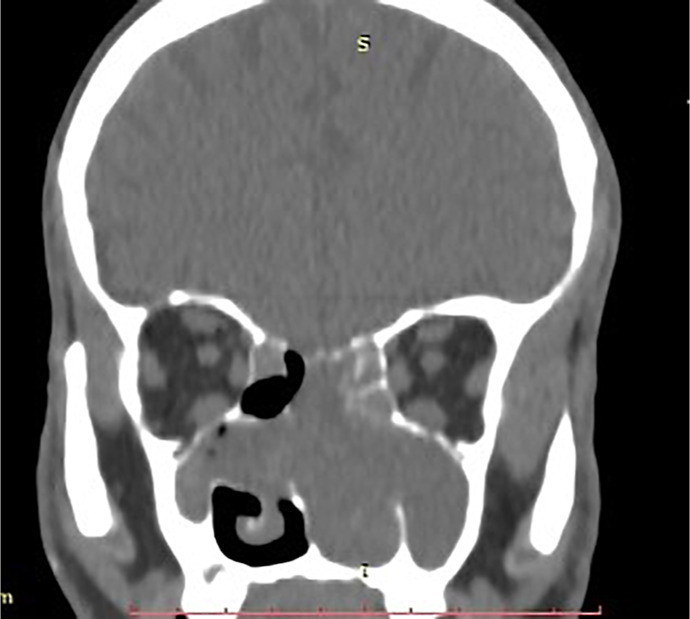

Case presentation: A 67-year-old male reported 10 months of nasal obstruction, mouth breathing, and sleep disturbances. The initial evaluation for foreign body obstruction revealed septal deviation and low-density sinonasal tissue on CT. MRI identified a 7 × 4.5 × 7 cm heterogeneous lesion invading nasal structures, paranasal sinuses, and nasopharynx with diffusion restriction. Tru-cut biopsy confirmed ACC via cribriform, tubular, and solid basaloid cell patterns, pseudocystic spaces, biphasic ductal-myoepithelial cells, and perineural invasion. Immunohistochemistry (CK7, CD117, p63, S100) supported the diagnosis, with tumor-free margins and no metastases. Multimodal therapy (30 VMAT sessions, 4 cisplatin-vinorelbine cycles) improved symptoms.

Abstract Image